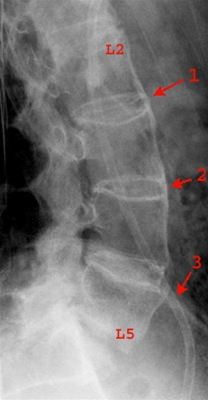

Rygsøjlen og SI-leddene kan undersøges med røntgen. Røntgen vil i de tidlige faser ikke vise noget. Ofte skal sygdommen have stået på i nogen tid, før skeletforandringerne bliver synlige ved en almindelig røntgenundersøgelse.

I de fremskredne stadier af Bechterew er røntgenfundene typiske og giver mulighed for at stille en sikker diagnose. De typiske forandringer ses i overgangen mellem lændehvirvlerne og bækkenknoglerne og i rummet mellem lændehvirvlerne.